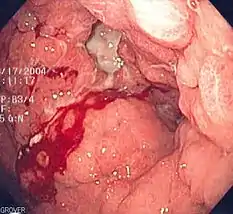

- Gastrointestinal

- Upper gastrointestinal bleed

- Lower gastrointestinal bleed

- Occult gastrointestinal bleed